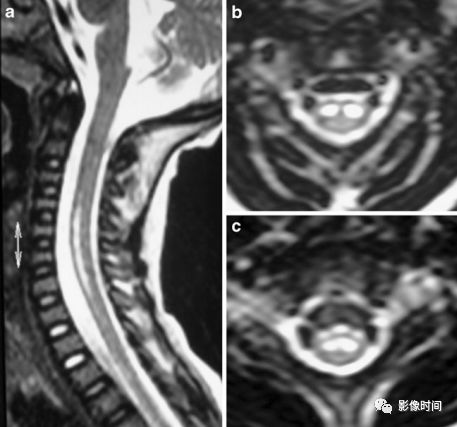

亚急性联合变性(Subacute combined degeneration,SCD)是由于维生素 B12 缺乏导致的脊髓变性疾病

MRI:

-

轴位图:脊髓后索「倒 V」或「倒兔耳」;病灶也可位于侧索

T1WI 病灶稍低信号,T2WI 稍高信号

无强化或强化

伴或不伴脑白质高信号

病灶分布于脊髓后索,T2WI高信号,呈倒“V”字征,明显强化